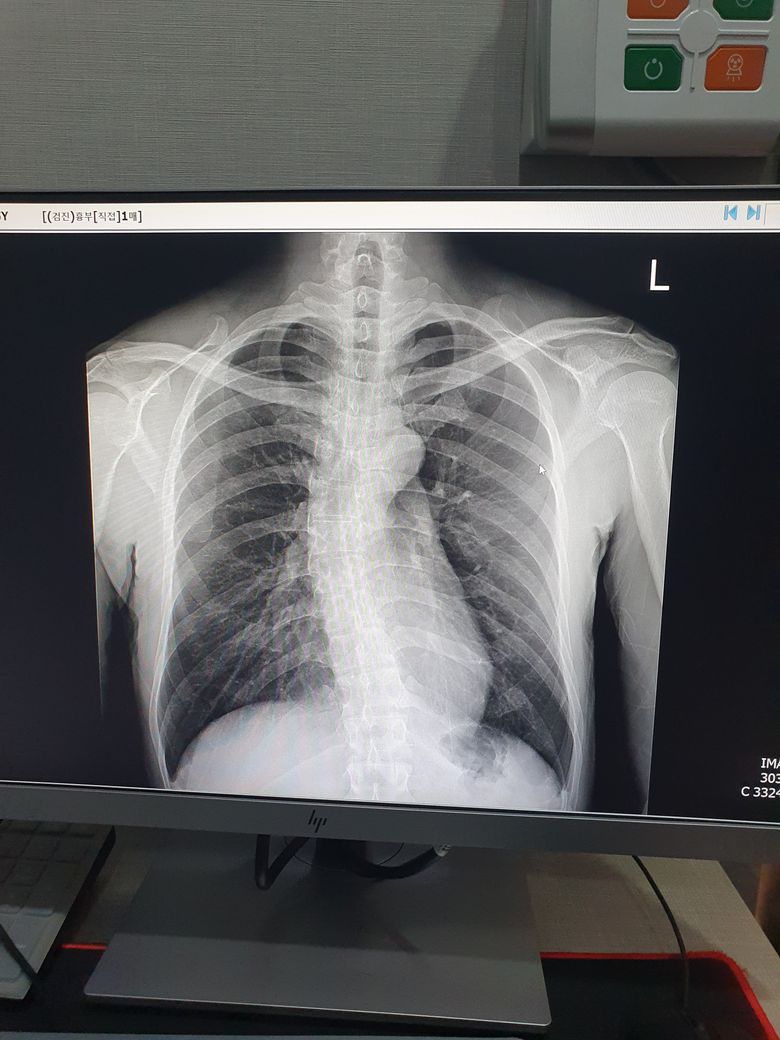

얼마전 건강검진 시 폐 엑스선에 짙은 음영이 발견되었습니다.

L 쪽, 보는방향에선 오른쪽 짙은 음영이 무엇일까요?

검진시 특별한 말씀은 없으셨는데 2년전 사진에선 안보이던 것이라 신경이 쓰여서요.

오른쪽에 어떤 병변을 말씀하시는지 정확치 않으나 가장자리쪽으로 하얗게 보이는 것을 말씀하시는 것이라면 이는 어깨뼈 (scapula) 가 비쳐 보이는 음영일 가능성이 높습니다. 양측성으로 관찰되고 있습니다.